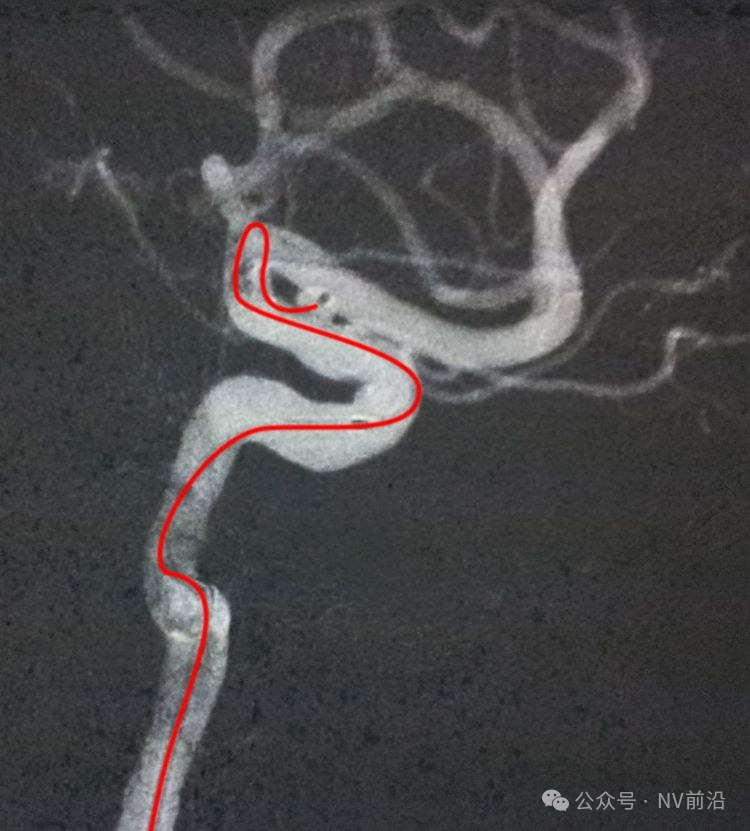

病例一,左侧微小眼动脉瘤,未破裂。

测量:瘤体2.09×2.34 mm,颈宽2.66 mm。

工作位造影

Traxcess 14微导丝可以进入瘤腔,但头端塑成S形的Echelon 10微导管无法跟入。

将微导管在虹吸弯处成襻,越过瘤颈,管头折返钩入瘤腔,即所谓回马枪技术。